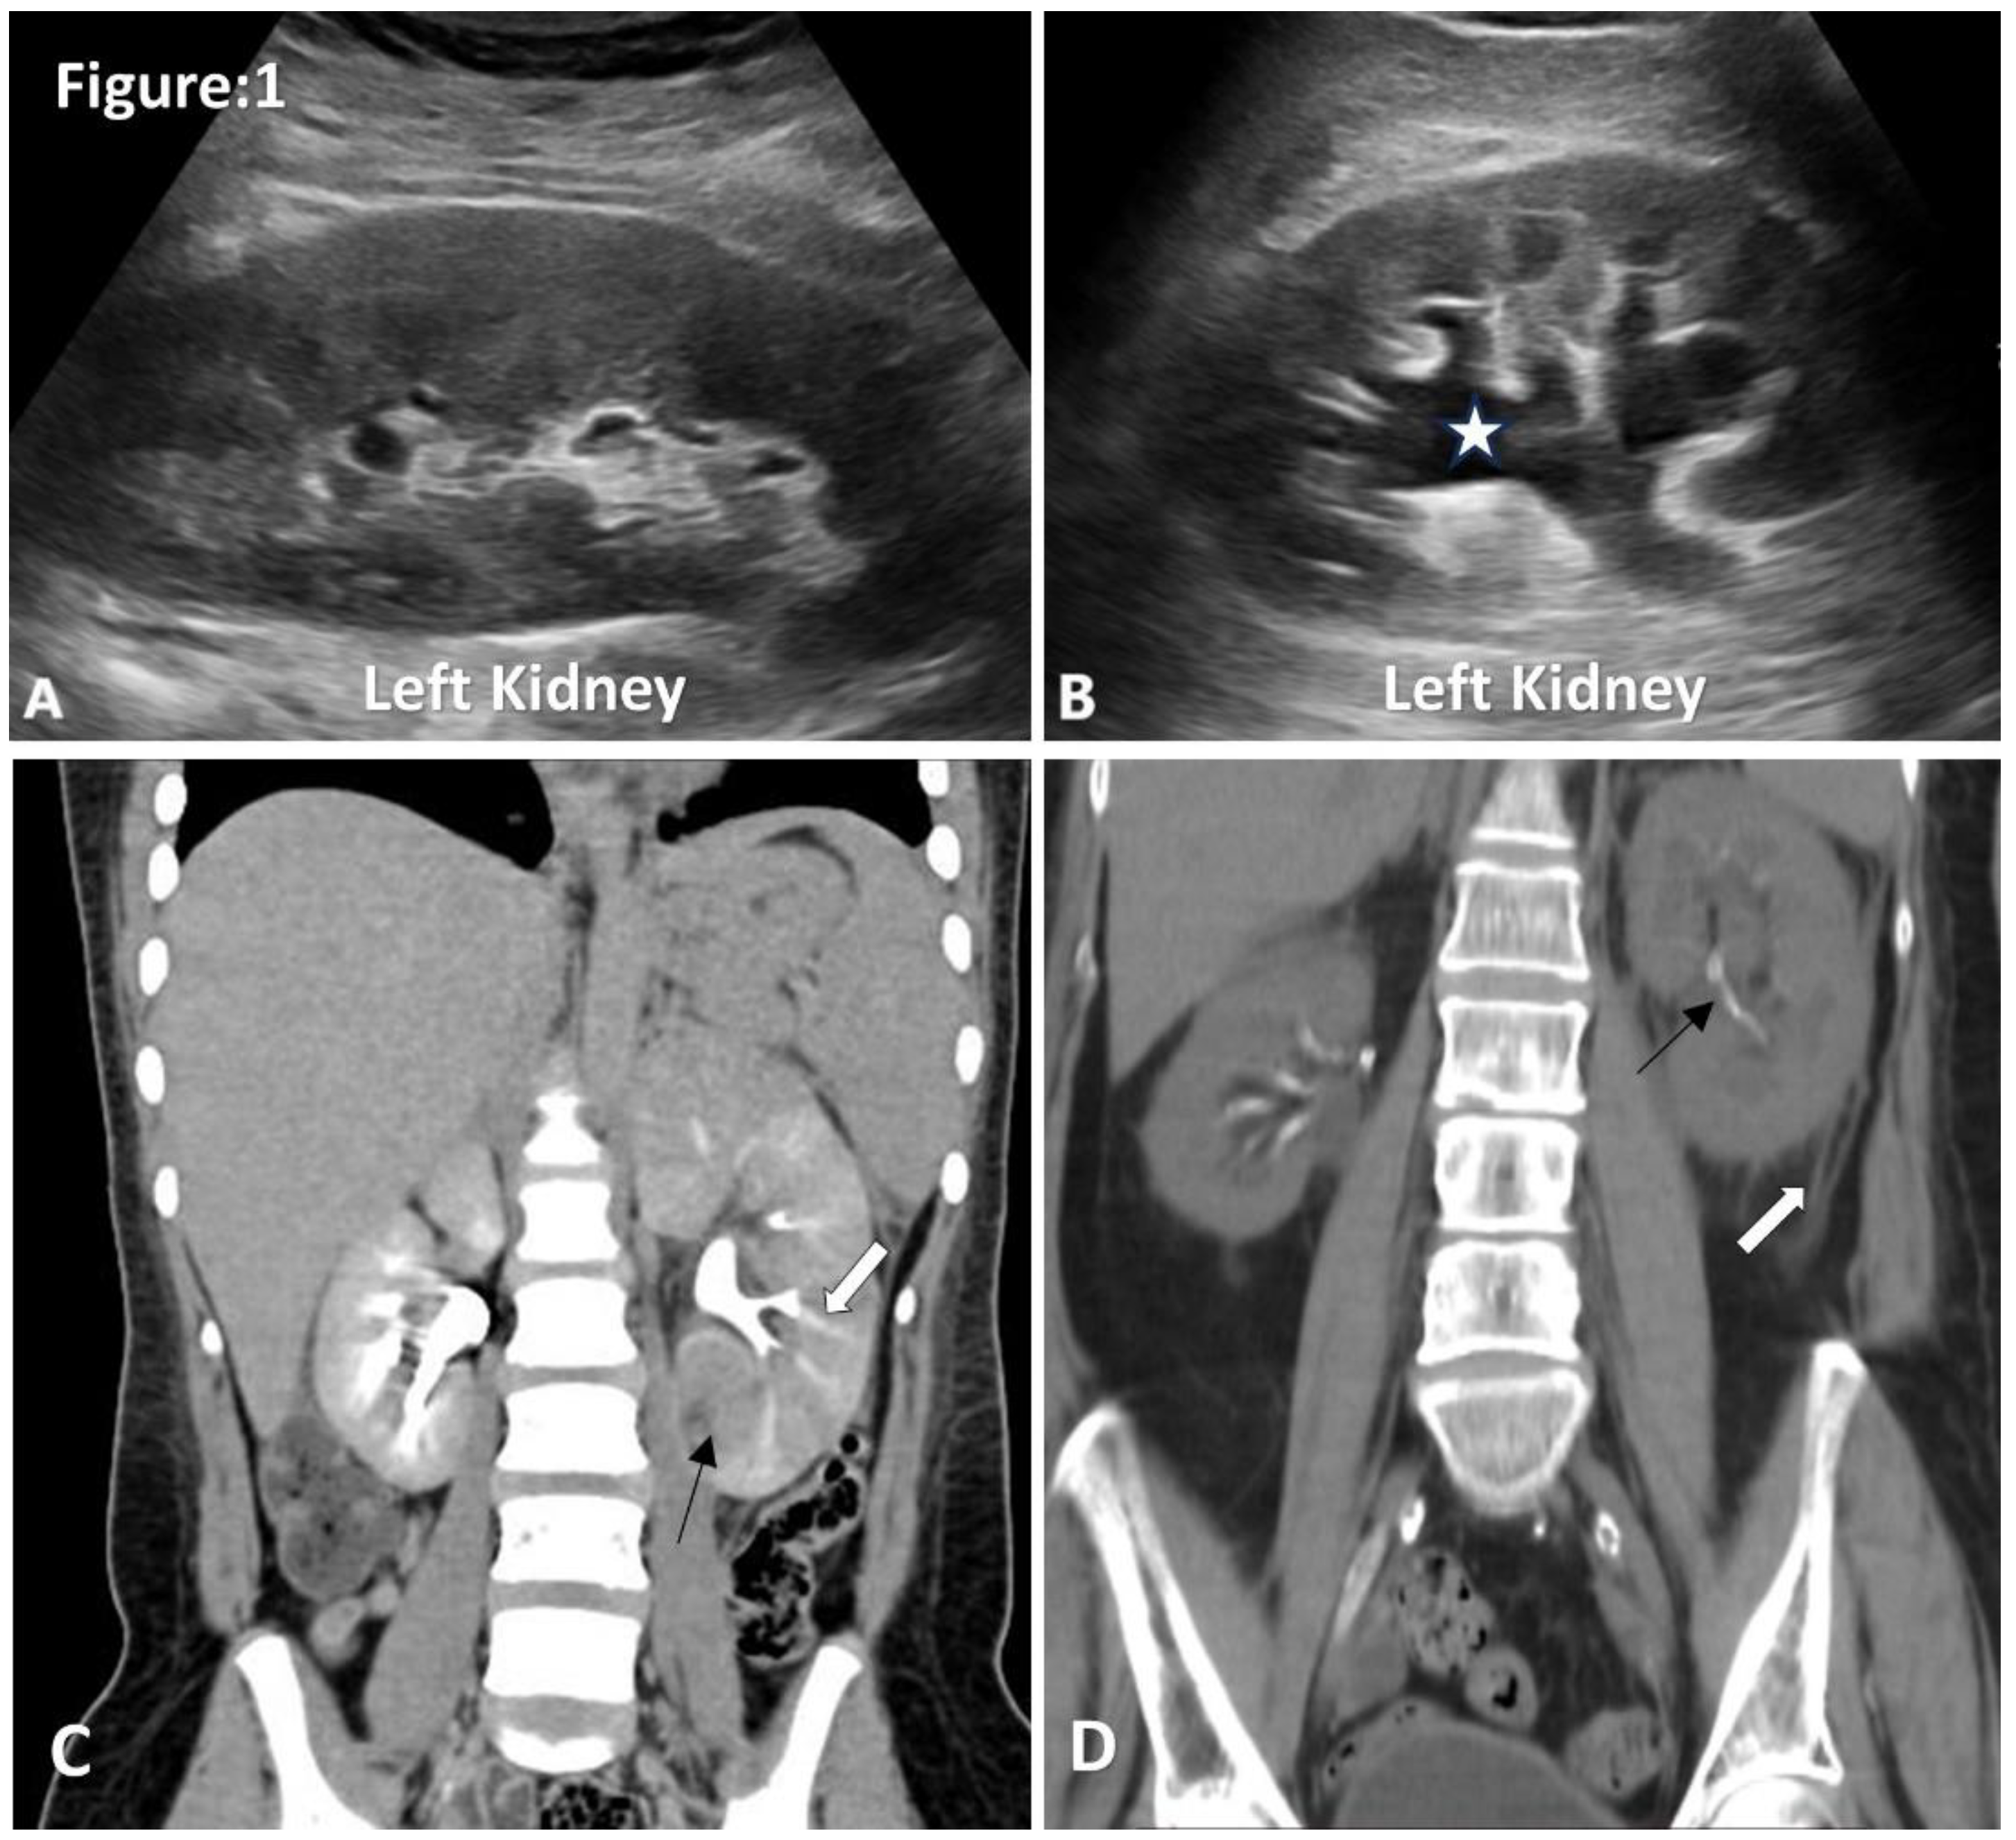

Acute Pyelonephritis

Acute Focal Bacterial Nephritis

Renal and Perinephric Abscesses

Pyonephrosis

Xanthogranulomatous Pyelonephritis